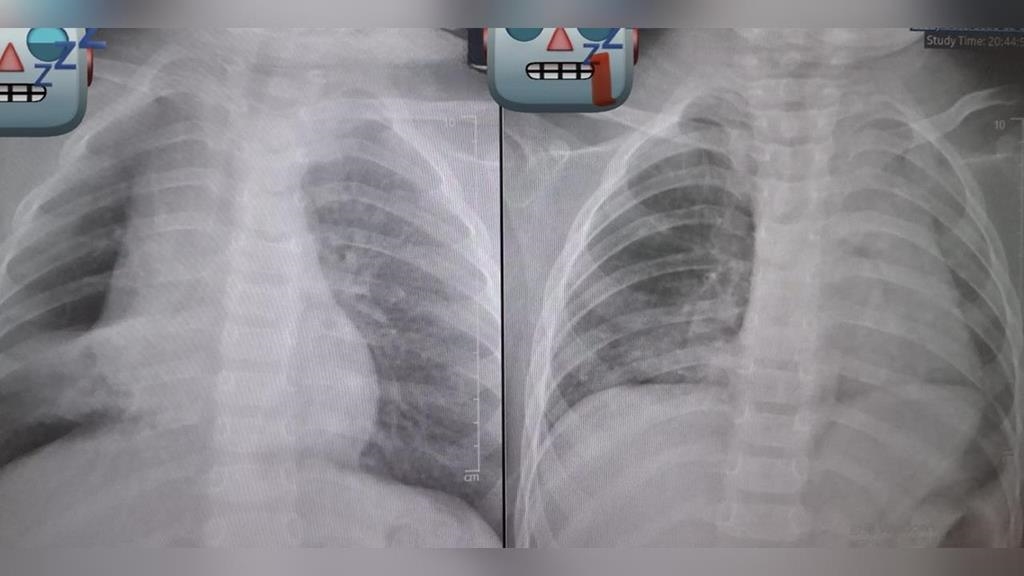

花生卡氣管 3 天長肉芽,追蹤X光後發現孩童的「肺部已經開始塌陷」。(圖/「廖穗綾醫師的健兒門診-Hablo Español」授權提供)

基隆長庚醫院兒科教授級主治醫師廖穗綾今(12日)在臉書粉專發文指出,上週原本要和家人去吃大餐,卻臨時接到一名緊急轉送來的1歲多病童,了解事發經過後,孩子3、4天前阿嬤餵食孫子一整顆花生,接著便開始出現咳嗽與喘鳴聲,雖然剛開始症狀不明顯,但隔天追蹤X光後發現孩童的「肺部已經開始塌陷」,直呼不能輕忽。廖醫師的丈夫賴醫師緊急召集加護病房團隊與資深技術員,準備進行手術。然而手術過程異常艱難,廖穗綾描述,那顆花生已經卡了3天,周圍長出了肉芽,「整顆又大又肥,死死塞住支氣管」,賴醫師表示從來沒有遇到這麼困難的案例,經過長達2個小時的搶救,才把那顆「會跳舞的花生」成功網住、夾出。